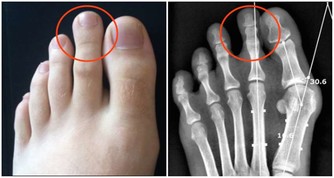

洗牙之後會覺得牙齒鬆了,這是因為牙周炎患者普遍存在嚴重的牙結石,

牙結石像水泥牆一樣粘在牙齒周圍,把所有牙齒全部捆在一起,讓你感覺牙齒看起來看很牢固,

所以當洗牙之後,把牙結石清掉,就會感覺牙縫大了,牙齒鬆了。

其實牙結石清掉,等待炎症消除後,這些情況都會改善的。